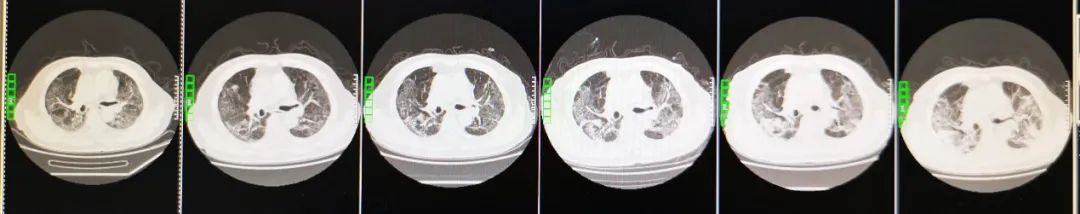

病程中患者胸部CT变化:

(从左至右)3-13,3-5,3-1,2-23,2-18,2-12

患者于2月12日行胸部CT,影像学表现为两肺感染性病变,考虑病毒性肺炎。两肺见弥漫分布磨玻璃影,纵膈窗显示两肺门无增大,气管支气管通畅,纵膈未见肿大淋巴结,心脏、大血管未见异常。我们还注意到病人肺部CT的前后变化对比:2020年2月18日:两肺病灶较前相仿。2020年2月23日:两肺病灶较前相仿。2020年3月1日:较前稍吸收。2020年3月5日:两肺病灶较前部分吸收好转。2020年3月13日:较前进一步吸收好转。